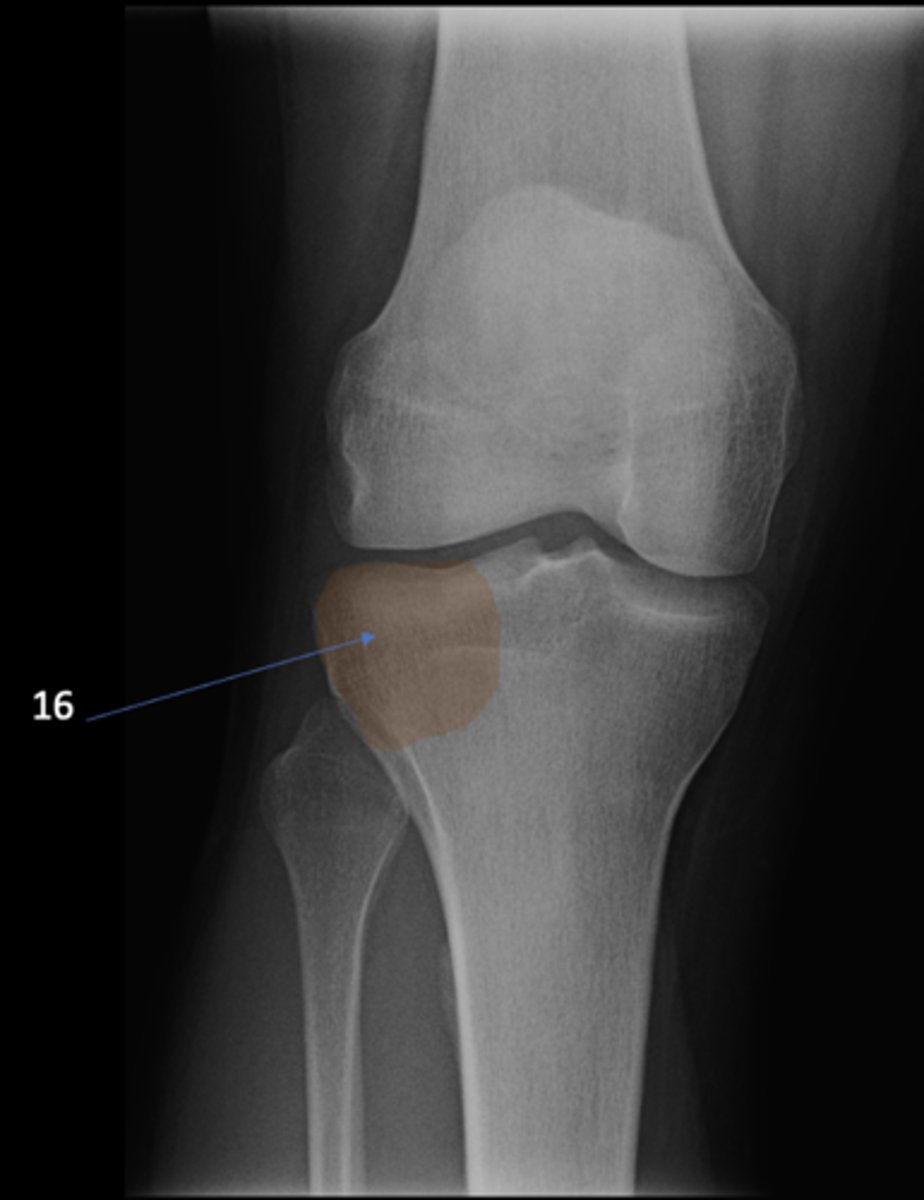

49

New cards

Fibular head

ID 1

64

Lateral tibial condyle

ID 16

<p>ID 16</p>